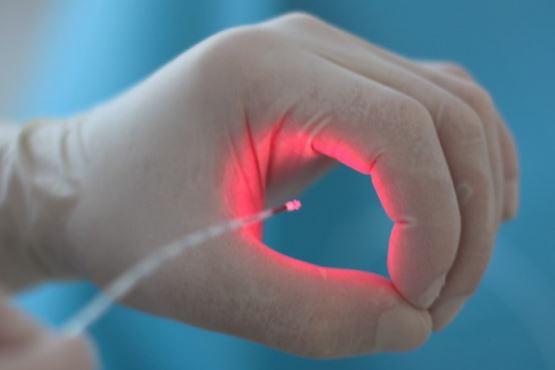

- Θεραπεία αιμορροϊδων με laser (LHP)

- Αφαίρεση αιμορροΐδων με υπερήχους (HALL-RAR)

- Xωρίς Χειρουργείο με ελαστικούς δακτυλίους (Τεχνική BARON-RBL)

- Θεραπεία αιμορροϊδων με laser (LHP)

- Αφαίρεση αιμορροΐδων με υπερήχους (HALL-RAR)

- Xωρίς Χειρουργείο με ελαστικούς δακτυλίους (Τεχνική BARON-RBL)

Ο Γενικός Χειρουργός Λιάγκος Γεώργιος MD PhD εκτελεί τις επεμβάσεις Λαπαροσκοπικά, Ενδοσκοπικά, Ανοιχτά Ελάχιστα Επεμβατικά και με Laser. Η θεραπεία εξατομικεύεται σε κάθε ασθενή ανάλογα με τις ανάγκες του. Αναλαμβάνει περιπτώσεις όπως κήλες και κοιλιοκήλες (αντιμετώπιση βουβωνοκήλης, αντιμετώπιση ομφαλοκήλης, θεραπεία επιγαστρικής κήλης, κήλη των αθλητών (Σύνδρομο κοιλιακών προσαγωγών), αντιμετώπιση μετεγχειρητικής κήλης, θεραπεία Μηροκήλης), πέτρες στη χοληδόχο κύστη, λαπαροσκοπική χολοκυστεκτομή, αντιμετώπιση Κύστη Κόκκυγος με λέιζερ (laser), παθήσεις πρωκτού, χειρουργική laser σύγχρονων κυκλικών ινών (αιμορροΐδες αντιμετώπιση, θεραπεία αιμορροϊδων με laser (LHP), αφαίρεση αιμορροΐδων με υπερήχους (HALL-RAR), χωρίς Χειρουργείο με ελαστικούς δακτυλίους (Τεχνική BARON-RBL), θεραπεία ραγάδας πρωκτού (Ραγάδα δακτυλίου), θεραπεία περιεδρικού συριγγίου, θεραπεία περιεδρικού αποστήματος, κονδυλώματα πρωκτού Θεραπεία, δερματικό ράκος (Skin tag) εκτομή, αντιμετώπιση Kνησμού, καρκίνος πρωκτού θεραπεία), παθήσεις Δέρματος, χειρουργική με laser CO2, αφαίρεση μορφωμάτων δέρματος - βιοψίες, αφαίρεση ελιάς (Σπίλου), σμηγματογόνος κύστης θεραπεία, αφαίρεση λιπώματος, είσφρυση όνυχος χειρουργείο, καρκίνος δέρματος θεραπεία, οξεία σκωληκοειδίτιδα, παθήσεις Λεπτού και Παχέος Εντέρου, ειλεός λεπτού εντέρου, εκκολπωμάτωση (Εκκολπωματίτιδα) σιγμοειδούς, καρκίνος παχέος εντέου, κολοστομίες, port χημειοθεραπείας κ.α.

Ο Γενικός Χειρουργός Λιάγκος Γεώργιος MD PhD εκτελεί τις επεμβάσεις Λαπαροσκοπικά, Ενδοσκοπικά, Ανοιχτά Ελάχιστα Επεμβατικά και με Laser. Η θεραπεία εξατομικεύεται σε κάθε ασθενή ανάλογα με τις ανάγκες του. Αναλαμβάνει περιπτώσεις όπως κήλες και κοιλιοκήλες (αντιμετώπιση βουβωνοκήλης, αντιμετώπιση ομφαλοκήλης, θεραπεία επιγαστρικής κήλης, κήλη των αθλητών (Σύνδρομο κοιλιακών προσαγωγών), αντιμετώπιση μετεγχειρητικής κήλης, θεραπεία Μηροκήλης), πέτρες στη χοληδόχο κύστη, λαπαροσκοπική χολοκυστεκτομή, αντιμετώπιση Κύστη Κόκκυγος με λέιζερ (laser), παθήσεις πρωκτού, χειρουργική laser σύγχρονων κυκλικών ινών (αιμορροΐδες αντιμετώπιση, θεραπεία αιμορροϊδων με laser (LHP), αφαίρεση αιμορροΐδων με υπερήχους (HALL-RAR), χωρίς Χειρουργείο με ελαστικούς δακτυλίους (Τεχνική BARON-RBL), θεραπεία ραγάδας πρωκτού (Ραγάδα δακτυλίου), θεραπεία περιεδρικού συριγγίου, θεραπεία περιεδρικού αποστήματος, κονδυλώματα πρωκτού Θεραπεία, δερματικό ράκος (Skin tag) εκτομή, αντιμετώπιση Kνησμού, καρκίνος πρωκτού θεραπεία), παθήσεις Δέρματος, χειρουργική με laser CO2, αφαίρεση μορφωμάτων δέρματος - βιοψίες, αφαίρεση ελιάς (Σπίλου), σμηγματογόνος κύστης θεραπεία, αφαίρεση λιπώματος, είσφρυση όνυχος χειρουργείο, καρκίνος δέρματος θεραπεία, οξεία σκωληκοειδίτιδα, παθήσεις Λεπτού και Παχέος Εντέρου, ειλεός λεπτού εντέρου, εκκολπωμάτωση (Εκκολπωματίτιδα) σιγμοειδούς, καρκίνος παχέος εντέου, κολοστομίες, port χημειοθεραπείας κ.α.